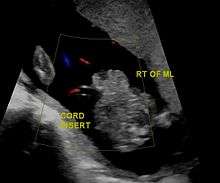

Widespread use of antenatal ultrasound examination and maternal serum alpha-fetoprotein (MSAFP) screening has made the detection of gastroschisis possible in the second trimester of pregnancy.[4]